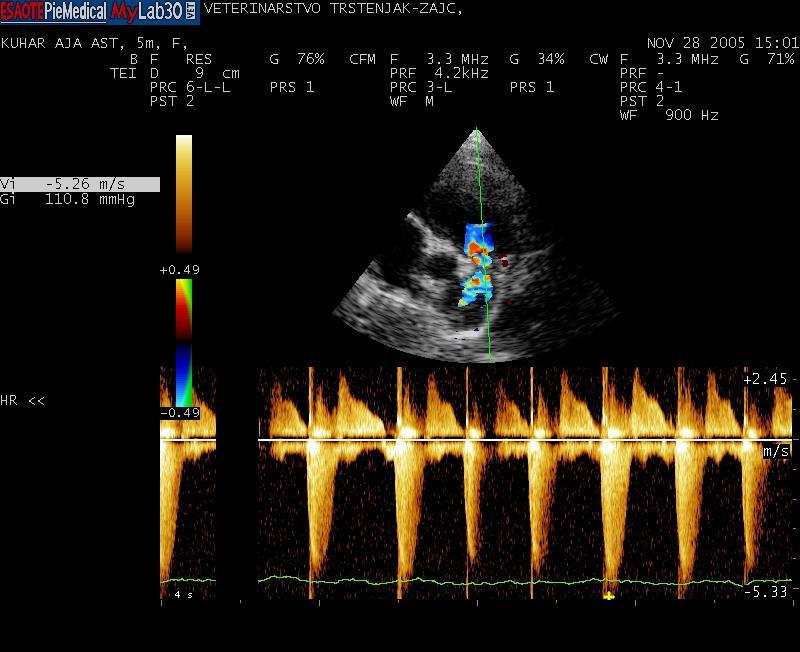

Kadar veterinar pri tem posumi na bolezen srca, je potreben celosten pregled kardiovaskularnega sistema, ki ga opravi veterinar – kardiolog. Ta večinoma obsega klinični pregled, ultrazvok srca, EKG in ob sumu na dekompenzacijo rentgen pljuč. To nam omogoči postavitev natančne diagnoze, ki je ključnega pomena za uspešnost terapije in dolgoročno prognozo.

Omenjene bolezni so le ene od tistih, s katerimi se srečujemo veterinarski kardiologi; seveda pa je srčnih obolenj še veliko več. Za uspešnost zdravljenja je največjega pomena natančna diagnoza. Te si v današnji veterinarski kardiologiji, ki v mnogih stvareh sledi humani medicini, ne moremo več predstavljati brez specialističnih preiskav. Sem sodi na prvem mestu ultrazvočna preiskava srca, ki je za postavitev diagnoze nepogrešljiva. Za celostno sliko obolenja pa večinoma potrebujemo še dodatne preiskave, kot so rentgensko slikanje pljuč, elektro kardiološka preiskava srčnega ritma, merjenje krvnega tlaka. Terapijo je nato potrebno natančno prilagoditi potrebam posameznega pacienta, saj se na zdravila ne odzovejo vsi enako. Tu je izjemnega pomena tesno sodelovanje in zaupanje med skrbnikom psa in izbranim veterinarjem – kardiologom. Le na tak način si zagotovimo optimalno kontrolo bolezni ter zadovoljstvo vseh: živali, njihovih skrbnikov ter ne nazadnje nas, kardiologov.